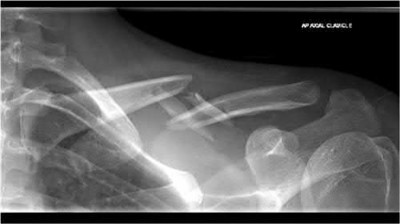

Figure A shows a radiograph of a 19-year-old male with an isolated shotgun injury. On physical examination, he has a 3 cm wound over the posterolateral aspect of his arm. In addition, he has weakness with wrist and finger extension, but no sensory deficits. The patient has received tetanus prophylaxis and antibiotics in the emergency department. What would be the next best steps in treatment?

This patient has sustained a shotgun blast to the midshaft humerus. The next best step would be irrigation and debridement, and external fixation of the fracture.

Shotgun injuries are typically treated as open fractures, whereas low-energy gunshot wounds are treated as closed fractures. The initial operative treatment of shotgun wounds should include irrigation and debridement and stabilization with external fixation. The goal of treatment is to stabilize the severe soft-tissue injury and bone loss, as well as to aggressively debride devitalized tissue and gross contamination.

Dougherty et al. reviewed gunshot fractures to the humerus. They report that

peripheral nerve injuries are relatively common with these injuries, with a more common incidence in distal injuries than proximal.

Joshi et al. looked at low velocity gunshot fractures to the humerus. They found that these injuries can be safely treated as closed fractures with local wound care, fracture brace and oral antibiotics. The time to union was similar in the non-operative and open treatment group.

Berick et al. examined the indications for nerve exploration with humerus gunshot fractures. They recommend continued observation of isolated nerve palsies associated with gunshot fractures of the humerus. However, consider early nerve exploration of palsies when associated with a concomitant vascular injury.

Figure A shows a high velocity shotgun fracture to the left humerus with retained buck fragments. Illustration A shows a similar injury stabilized with external fixation.